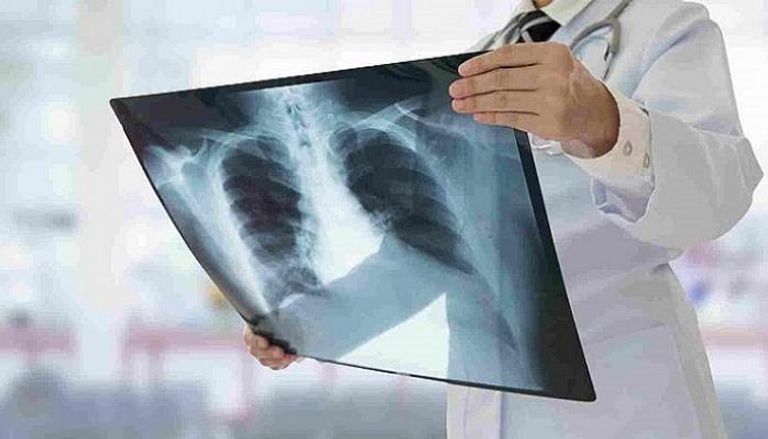

وبعد إجراء فحوصات التصوير المقطعي المحوسب والتصوير بالرنين المغناطيسي، وجد الأطباء ظلالًا مشبوهة في رئته اليمنى السفلية، وأظهر تنظير القصبات لاحقًا أن المريض يعاني من مرض فطري في الرئة ناتج عن عدوى الرشاشيات. عند سؤاله عن الأسباب المحتملة للعدوى، علم الأطباء أن الرجل قد اكتسب عادة شم جواربه المتسخة.

وأثناء استجوابه للمريض الذي لم يُكشف عن اسمه عن منزله ومدى جودة دوران الهواء فيه، علم الطبيب ليانغ بيكانغ، الطبيب المعالج في قسم أمراض الجهاز التنفسي بمستشفى ساوث ويست، أن الرجل كان يشم جواربه المتسخة كلما عاد إلى المنزل من العمل، قبل أن يرميها في الغسالة. وبعد أخذ زوج من جواربه المتسخة وتحليلها، وجد الأطباء آثارًا لفطر الرشاشيات، وقرروا أن عادته غير الصحية هي سبب العدوى.